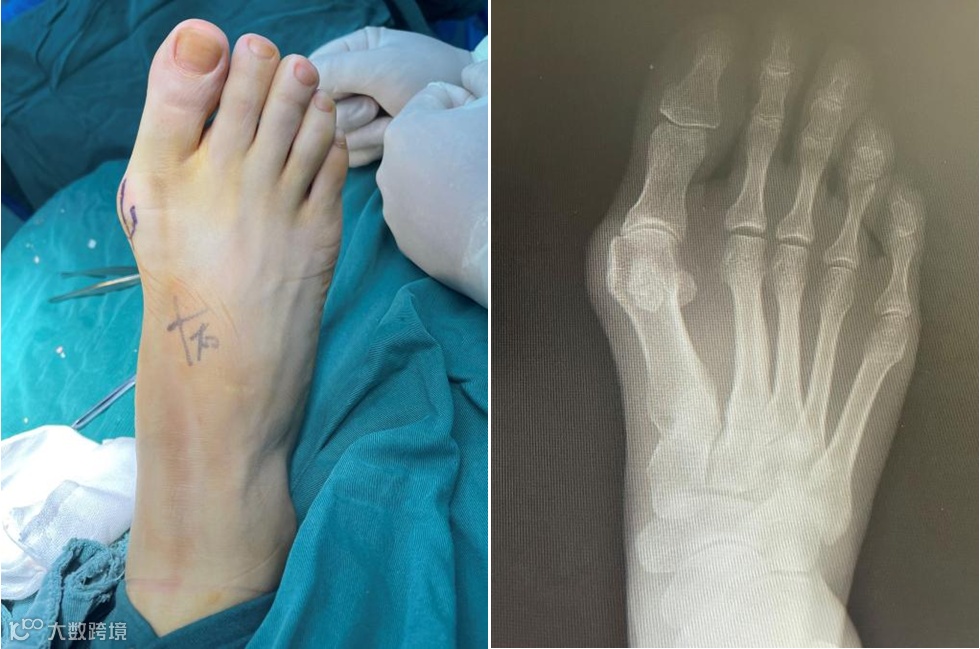

其实,小米也曾到外院就诊过,当时诊断为拇外翻畸形,医生建议其手术治疗。但出于对开刀手术的恐惧,她一直没有行动。近日在老公的鼓励下,她终于鼓起勇气来我科手术治疗。

创伤骨科郑进昌副主任医师接诊了小米,了解到她的情况后,告知该病通过微创手术就能矫正“大脚骨”的外观,且术后不会再觉得疼痛,能恢复正常跑步训练,也能穿上她心爱的高跟鞋。

入院当日医生对小米开展相关检查,第二日即行踇外翻畸形矫形术,耗时仅30分钟即术毕。为了带给小米更佳的治疗体验,主刀医师使用了皮内缝合术,让小米的脚几乎不留疤痕,术后第一天即可下地活动。

部分地区俗称大脚骨,是指拇趾在第一跖趾关节处向外侧偏斜移位。

拇外翻是一种复杂的解剖畸形,并且在治疗上极具挑战性。拇外翻是累及拇趾的最常见的病变,疼痛程度与畸形程度不相关,即轻度畸形即可能引发剧烈疼痛并影响生活。遗传是拇外翻发病的一个重要因素,尤其在青少年患者,拇外翻的发生可能与穿鞋不合适有重要关系。拇外翻也常见于系统性关节病患者中。